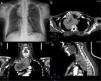

Case 1A 61-year-old woman was referred to our center with a 12-month history of subclinical hyperthyroidism. She had undergone subtotal thyroidectomy for a multinodular goiter seven years previously in another center. Thyroid function tests revealed hyperthyroidism. Computed tomography (CT) showed the retrotracheal cervical thyroid in continuity with the posterior mediastinal mass that extended beyond the aortic arch and the azygos vein (Fig. 1). The goiter was causing left shift of the trachea and the esophagus, terminating at the level of the left atrium, below the carina tracheae. Examination of the larynx excluded recurrent nerve paralysis. Spirometry results showed forced vital capacity (FVC) of 3.62 l (109%) and forced expiratory volume in 1 second (FEV1) of 2.88 l (114%).

Case 2A 64-year-old woman was admitted to our center due to a 6-month history of IG. The IG had been identified during a routine evaluation of atrial fibrillation. Thyroid function tests were normal. CT revealed a lobulated mass in the thyroid gland adjacent to the lower pole of the right thyroid lobe (Fig. 2). The mass was seen to extend in a retrotracheal direction to a distance of 3cm below the carina tracheae. Spirometry results showed an FVC of 2.63 l (60%) and an FEV1 of 1.92 l (62%).